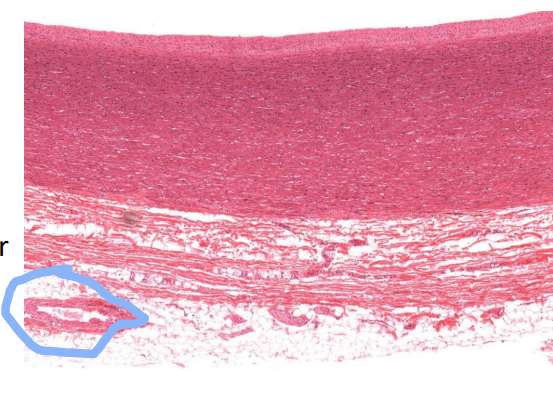

Identify this structure

Epicardium of the ventricle

What makes up the epicardium?

Outer mesothelial cells (often missing)

Supported by DICT

Loose CT = unilocular adipose

Identify the structure and the tissue indicated by the arrow

Epicardium of the atrium